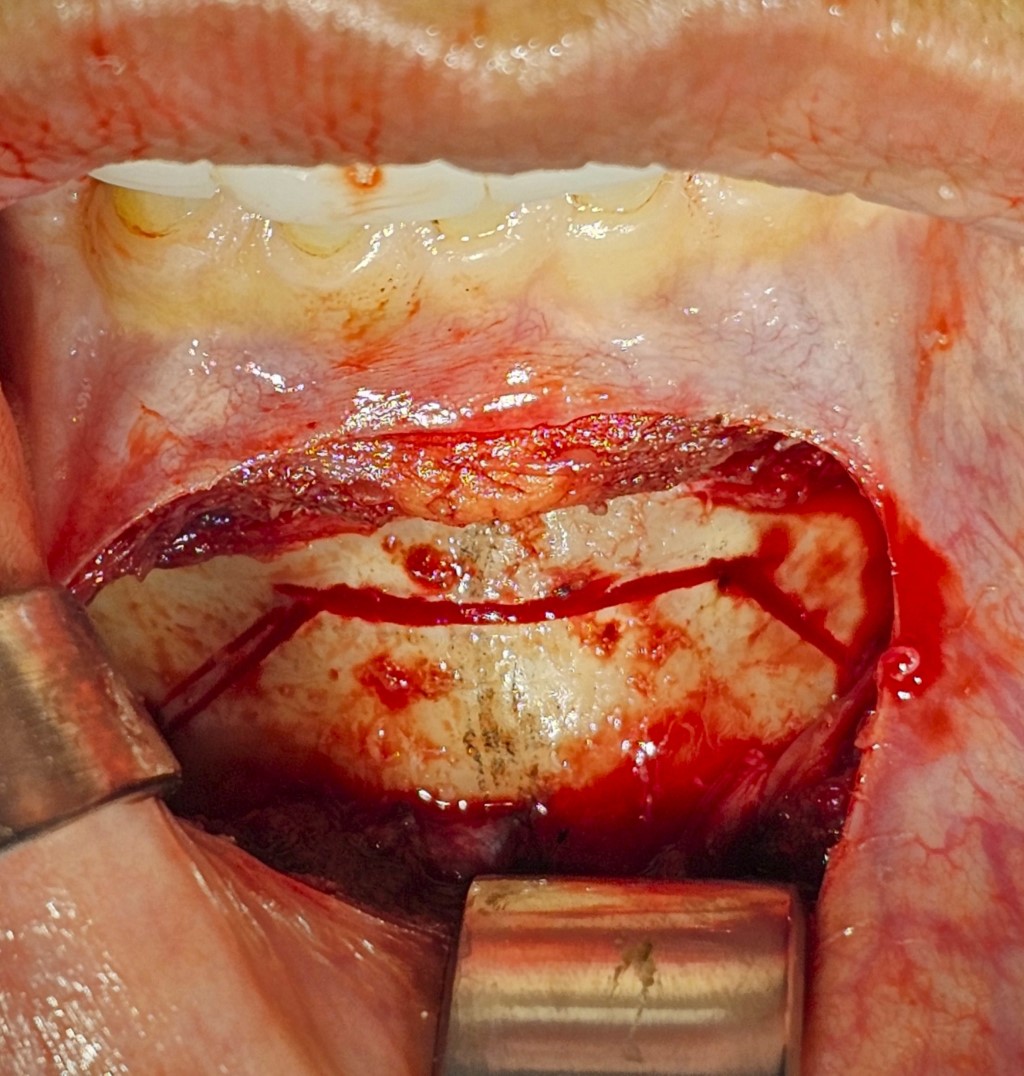

New genioplasty technique that preserves the mentolabial fold: technical note

Chin surgery is one of the surgical procedures that has the greatest impact on facial harmony. Since it involves the lower third of the face, it is crucial to consider the mentolabial fold as a key component in achieving both aesthetic and functional outcomes. The objective of this article is to propose a new mentoplasty technique for patients presenting with an adequate mentolabial fold but requiring correction of vertical macrogenia and horizontal microgenia, by excluding the mentolabial fold and/or the point of maximum mandibular concavity (Point B) from the osteotomy, and modifying only the projection of the Pogonion (Pg) through counterclockwise rotation. The trapezoidal-shaped osteotomy is performed via a minimally invasive approach, where the vertical cuts are camouflaged by the depressor anguli oris and depressor labii inferioris muscles to prevent notching. This technique aims to achieve aesthetic improvements by enhancing the projection of the Pg point, creating balance and harmony among the facial thirds, while preserving the position of Point B.

Figure 1

Figure 2

Figure 3

Figure 4